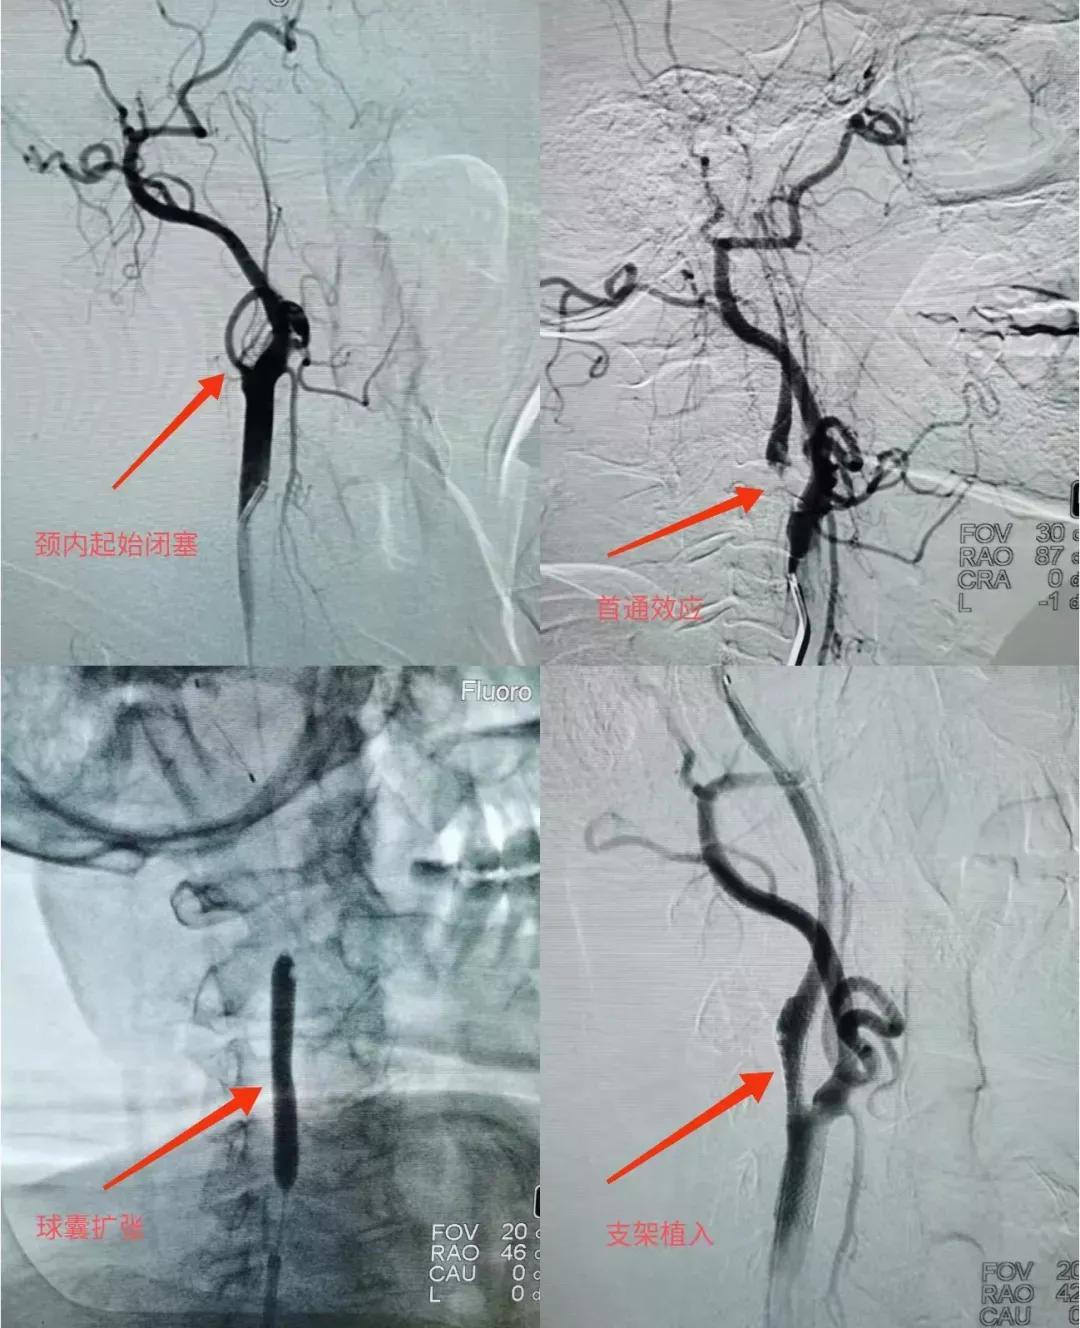

魏大爷脑血管造影显示:右侧颈内动脉起始处闭塞,王朝刚医师先进行颈内动脉取栓及支架植入术,再通过中间导管在病灶处抽吸出大量暗红色血栓,经过3个多小时的手术,术后魏大爷血管已经完全畅通,下肢肌力也恢复到3级(下肢可以稍微抬起),手术非常成功。

复查CT检查,未发现出血。